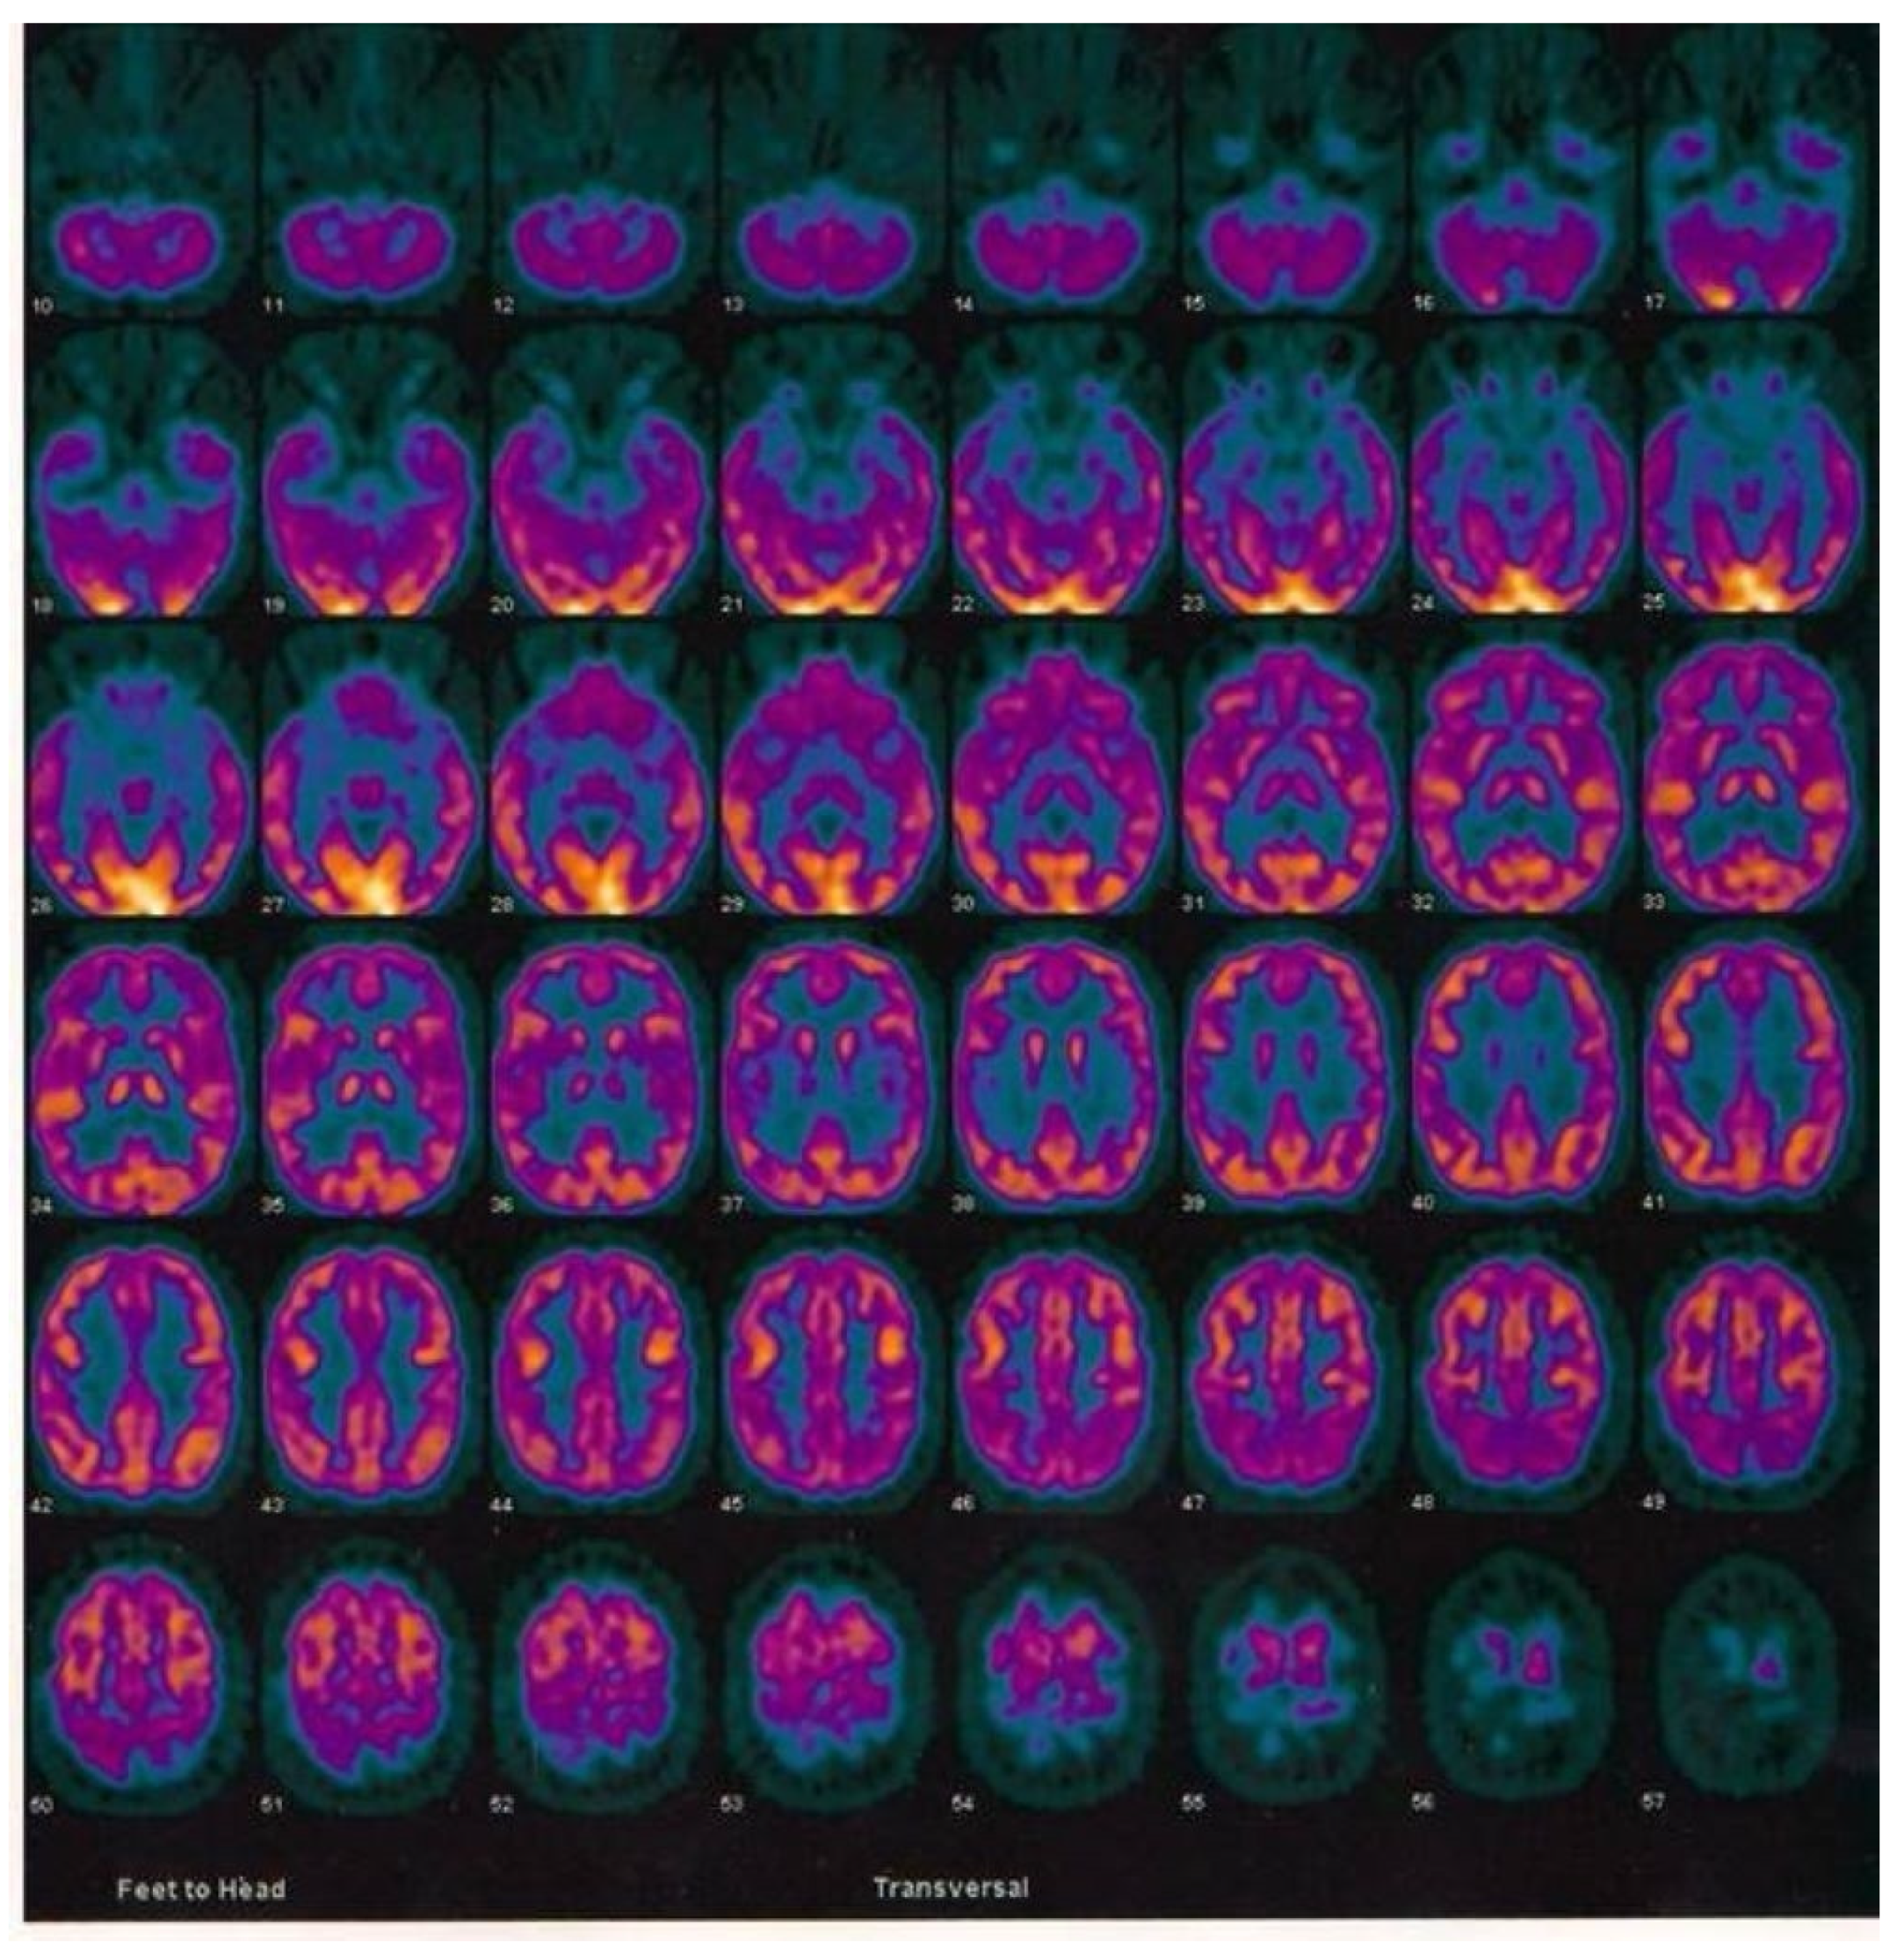

2.3. Case Report of One Patient in the CuAD Subgroup